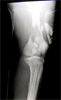

Malunion femur with Knee osteoarthritis in a 54 years old female Chinese

Open comminuted fracture femur treeated with debridement and external fixator

Pre

Op

Later,treated with acute shortening and stabilsation wit Ilizarove fixator for chronic osteomyelitis